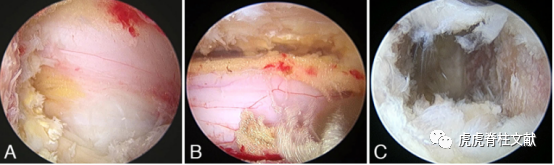

2.术中内镜图像,显示中央管减压和同侧椎板切除(A),对侧椎板下减压(B),以及处理后的软骨终板(C)